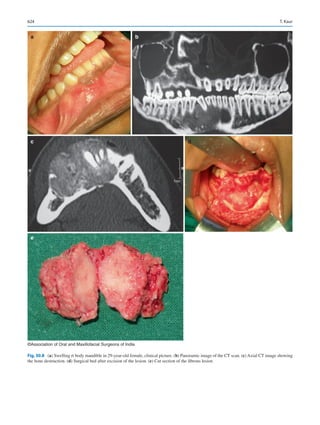

Partial seizures—start in a localized area [25].

3.6.1.1  Basic considerations

While recording history, the duration, type, frequency of the

seizure as well as the most recent episode must be recorded

as well as the type of medication taken, if any. If the patient